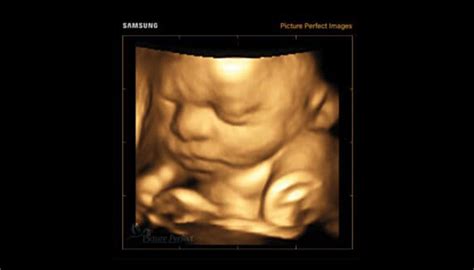

- Ecografii: Sunt disponibile ecografii ginecologice, ecografii de sarcină 3D/4D, precum și ecografii generale.